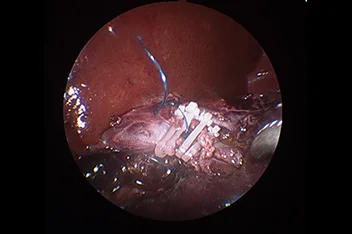

흉강경

복강경과 유사하게 최소 절개를 통해 흉강 수술을 진행하게 됩니다.

작은 구멍으로 카메라 포트가 진입하여 수술 부위를 시각화하고 진단과 치료를 진행할 수 있습니다.

흉강에서는 탐색과 조직생검을 통해 확실한 진단에 도움이 됩니다.

심낭수 치료를 위해 심낭막절제술, 최소침습 폐엽절제, 유미흉의 치료를 위한 흉관결찰(Thoracic duct ligation) 등이 진행될 수 있습니다.

흉강경심막절제술 (Preicardiectomy)

흉강경흉관결찰 (Thoracic duct ligation)

* 리본동물의료센터 케이스 사진으로 무단 복제 및 도용을 금지합니다.